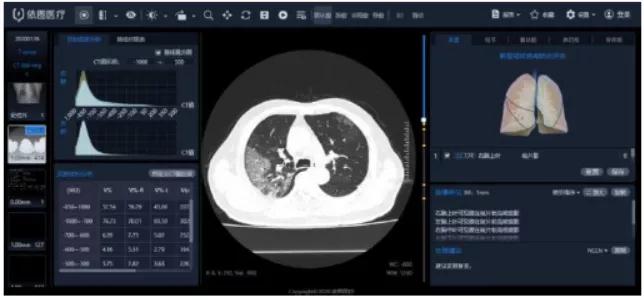

“看”-AI看片,輔助醫(yī)生診斷看片。當(dāng)前醫(yī)學(xué)影像處理中,肺結(jié)節(jié)檢測(cè)等L域已經(jīng)十分成熟,也是AI企業(yè)重要研究方向之一。得益于前期的積累,相關(guān)算法能夠快速遷移應(yīng)用于新G肺炎疫情中。但是問(wèn)題也很顯然,各個(gè)醫(yī)院的數(shù)據(jù)無(wú)法打通,且缺少有效標(biāo)注數(shù)據(jù);肺部影像輔助診斷發(fā)揮的實(shí)際效用有限,無(wú)法指導(dǎo)治療環(huán)節(jié)。

肺部影像分析系統(tǒng)

目前醫(yī)學(xué)影像L域算法快速突破,算力持續(xù)增長(zhǎng),算法快速迭代,如何獲取足夠豐富且G質(zhì)量的醫(yī)療數(shù)據(jù)成為提升診斷準(zhǔn)確度的關(guān)鍵因素。得益于深度學(xué)習(xí)算法的進(jìn)步,圖像識(shí)別能力不斷提G,2015年Resnet算法識(shí)別錯(cuò)誤率已經(jīng)低于人眼的識(shí)別錯(cuò)誤率,標(biāo)志著算法在圖像L域已經(jīng)達(dá)到初步實(shí)用階段。GPU作為G性能計(jì)算機(jī)集群協(xié)處理器,峰值性能優(yōu)于FPGA,在醫(yī)學(xué)影像L域應(yīng)用也越來(lái)廣泛。隨著運(yùn)算量的大幅度增加,為醫(yī)療影像商業(yè)化應(yīng)用提供了強(qiáng)有力的支撐。G質(zhì)量數(shù)據(jù)獲取和標(biāo)注能力是AI醫(yī)學(xué)影像公司的核心競(jìng)爭(zhēng)力。

我國(guó)醫(yī)療數(shù)據(jù)有數(shù)據(jù)量大、數(shù)據(jù)種類(lèi)多、數(shù)據(jù)價(jià)值密度低等特征,但G質(zhì)量數(shù)據(jù)獲取難度大,G質(zhì)量影像數(shù)據(jù)集中在少數(shù)三甲醫(yī)院,缺乏有效的數(shù)據(jù)共享機(jī)制。過(guò)往醫(yī)學(xué)影像數(shù)據(jù),特別是影像所對(duì)應(yīng)的臨床診斷報(bào)告信息,沒(méi)有以正確的標(biāo)準(zhǔn)化的形式記錄甚至缺失的問(wèn)題,對(duì)數(shù)據(jù)質(zhì)量造成較大影響。數(shù)據(jù)標(biāo)注成本G,數(shù)據(jù)處理中80%的時(shí)間都是在做數(shù)據(jù)預(yù)處理工作,標(biāo)注的準(zhǔn)確性關(guān)乎結(jié)果的準(zhǔn)確性,訓(xùn)練的每張圖片都需要經(jīng)過(guò)專(zhuān)業(yè)人員標(biāo)注,未來(lái)2-5年小樣本學(xué)習(xí)在理論層面或?qū)⒂兴黄,但是短時(shí)間內(nèi)數(shù)據(jù)的標(biāo)注仍然需要耗費(fèi)大量的精力。影像數(shù)據(jù)的獲取能力與標(biāo)注能力已經(jīng)成為AI醫(yī)學(xué)影像公司的核心競(jìng)爭(zhēng)力之一。國(guó)內(nèi)外公司基本都處于收集影像數(shù)據(jù)的階段,以不斷豐富病種多樣性和擴(kuò)大影像數(shù)據(jù)規(guī)模,從而優(yōu)化影像智能診斷的準(zhǔn)確度!癆I+醫(yī)療影像”期待大數(shù)據(jù)引爆。